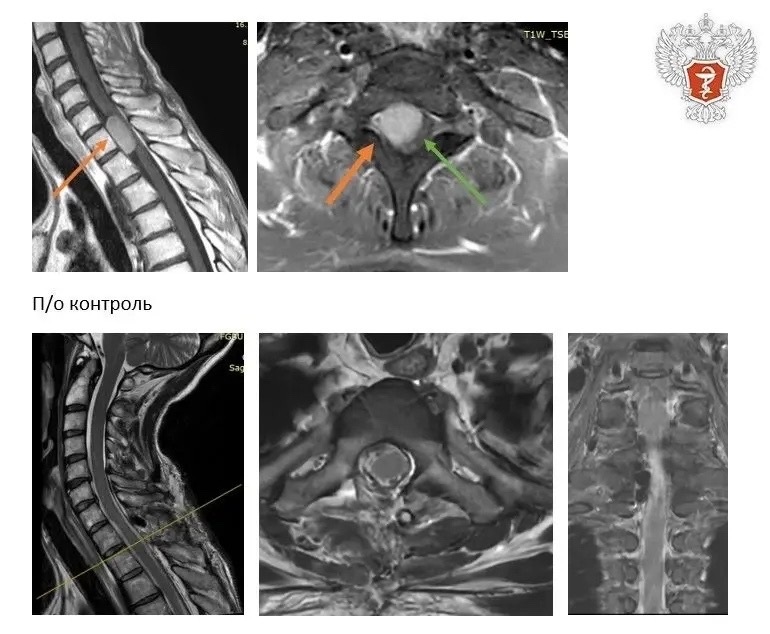

Новообразование располагалось спереди спинного мозга, что осложняло его хирургическое удаление.

❤️ Операция прошла успешно. Гистологическое исследование подтвердило, что образование — менингиома — доброкачественная опухоль. Сейчас пациентка чувствует себя хорошо, двигательные функции ног восстановлены.